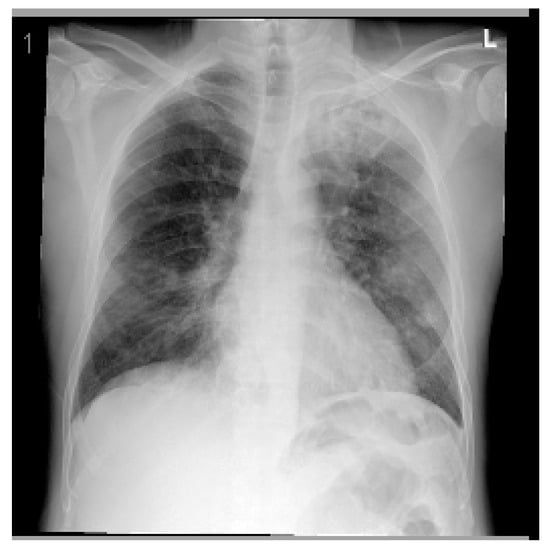

A summary of his laboratory and radiological investigations are described in Table 1 and Figure 1, respectively.

A CT chest with contrast was completed to confirm the CXR findings and was reported as: ‘Bilateral multiple patchy cavitating consolidations larger at the apical posterior segment of left upper lobe, differential diagnosis includes cavitating pneumonia, fungal infection or TB, especially with the involvement of the the apicoposterior segment and less likely to represent septic emboli’. The patient was admitted to the intensive care unit (ICU) with the impression of COVID-19 or TB pneumonia and acute coronary syndrome. The patient was examined by the Cardiology and Gastroenterology teams, who ruled out any significant conditions and placed him on conservative therapy.

Figure 1. Posteroanterior chest X-ray (CXR) of the first case. The CXR shows bilateral diffuse patchy opacities noted with left upper lung zone consolidation, which could be infectious for clinical correlation and follow-up. Perihilar peribronchial thickening noted. No pleural effusion or pneumothorax. The cardiomediastinal silhouette appears unremarkable.